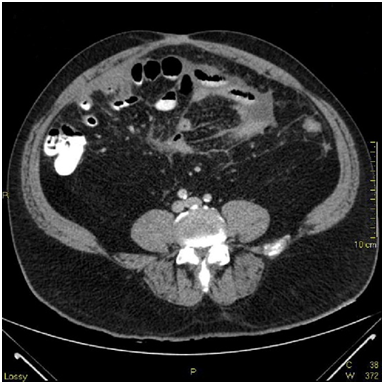

Admission labs showed a slight elevation in alkaline phosphatase, platelets and white blood cell count. There were no other major laboratory abnormalities and/or signs of infection. CT scan showed compartmentalized interloop hypodense fluid collection throughout the mesentery with associated fat stranding and small mesenteric nodules. (Images 1-3) There was encasement of small bowel loops, pleating of the mesentery and contraction of the peritoneal cavity. Mild small bowel dilatation without obstruction also noted.

CT scan is the main diagnostic tool with two distinct patterns on cross sectional images: (a) diffuse involvement of the peritoneal cavity and (b) focal intraperitoneal masses. Our patient presented with diffuse involvement of the peritoneal cavity without omental caking or masses. Small bowel encasement with interloop fluid and radial small bowel distribution was noted, as well as "stellate" mesentery due to tumoral infiltration. (Image 1,2,3) Differential diagnosis from imaging standpoint includes peritoneal infections such as tuberculosis, histoplasmosis and peritoneal carcinomatosis.6